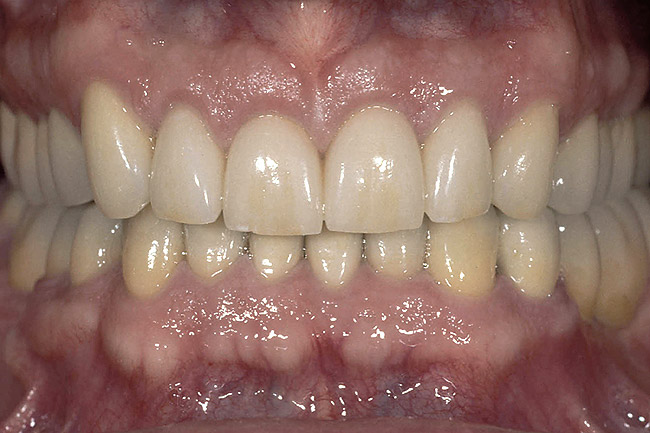

Figure 6  A patient presented with severe anterior wear and over-eruption. Esthetically, the maxillary centrals needed lengthening by 3 mm incisally.

Figure 6

Figure 7  A full-arch temporary was placed to correctly identify an acceptable incisal edge position prior to surgery.

Figure 7

Figure 8  Osseous crown lengthening was performed using the incisal edge position of the temporary to determine bone and gingival levels.

Figure 8

Figure 9  View at 10 weeks post-surgery showing the new gingival level. The preparation and temporary will now be extended to the gingival level.

Figure 9

Figure 10  The final restorations demonstrate the esthetic and functional changes from lengthening the incisal edges and raising the gingiva.

Figure 10